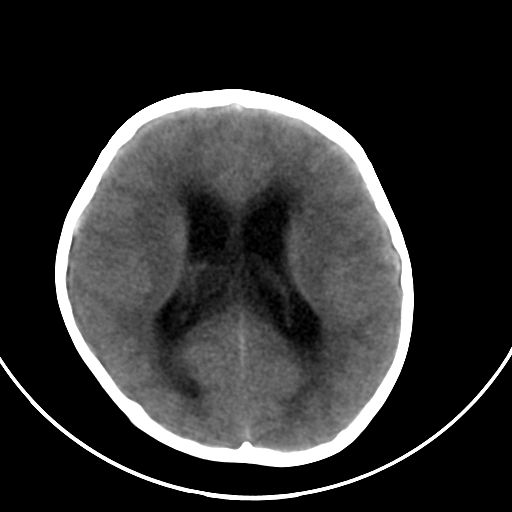

以下是引用zjzjr在2008-7-27 9:56:00的发言:[br]考虑髓母细胞瘤伴梗阻性脑积水.建议增强或mri

以下是引用子十在2008-7-27 9:53:00的发言:[br]考虑髓母细胞瘤